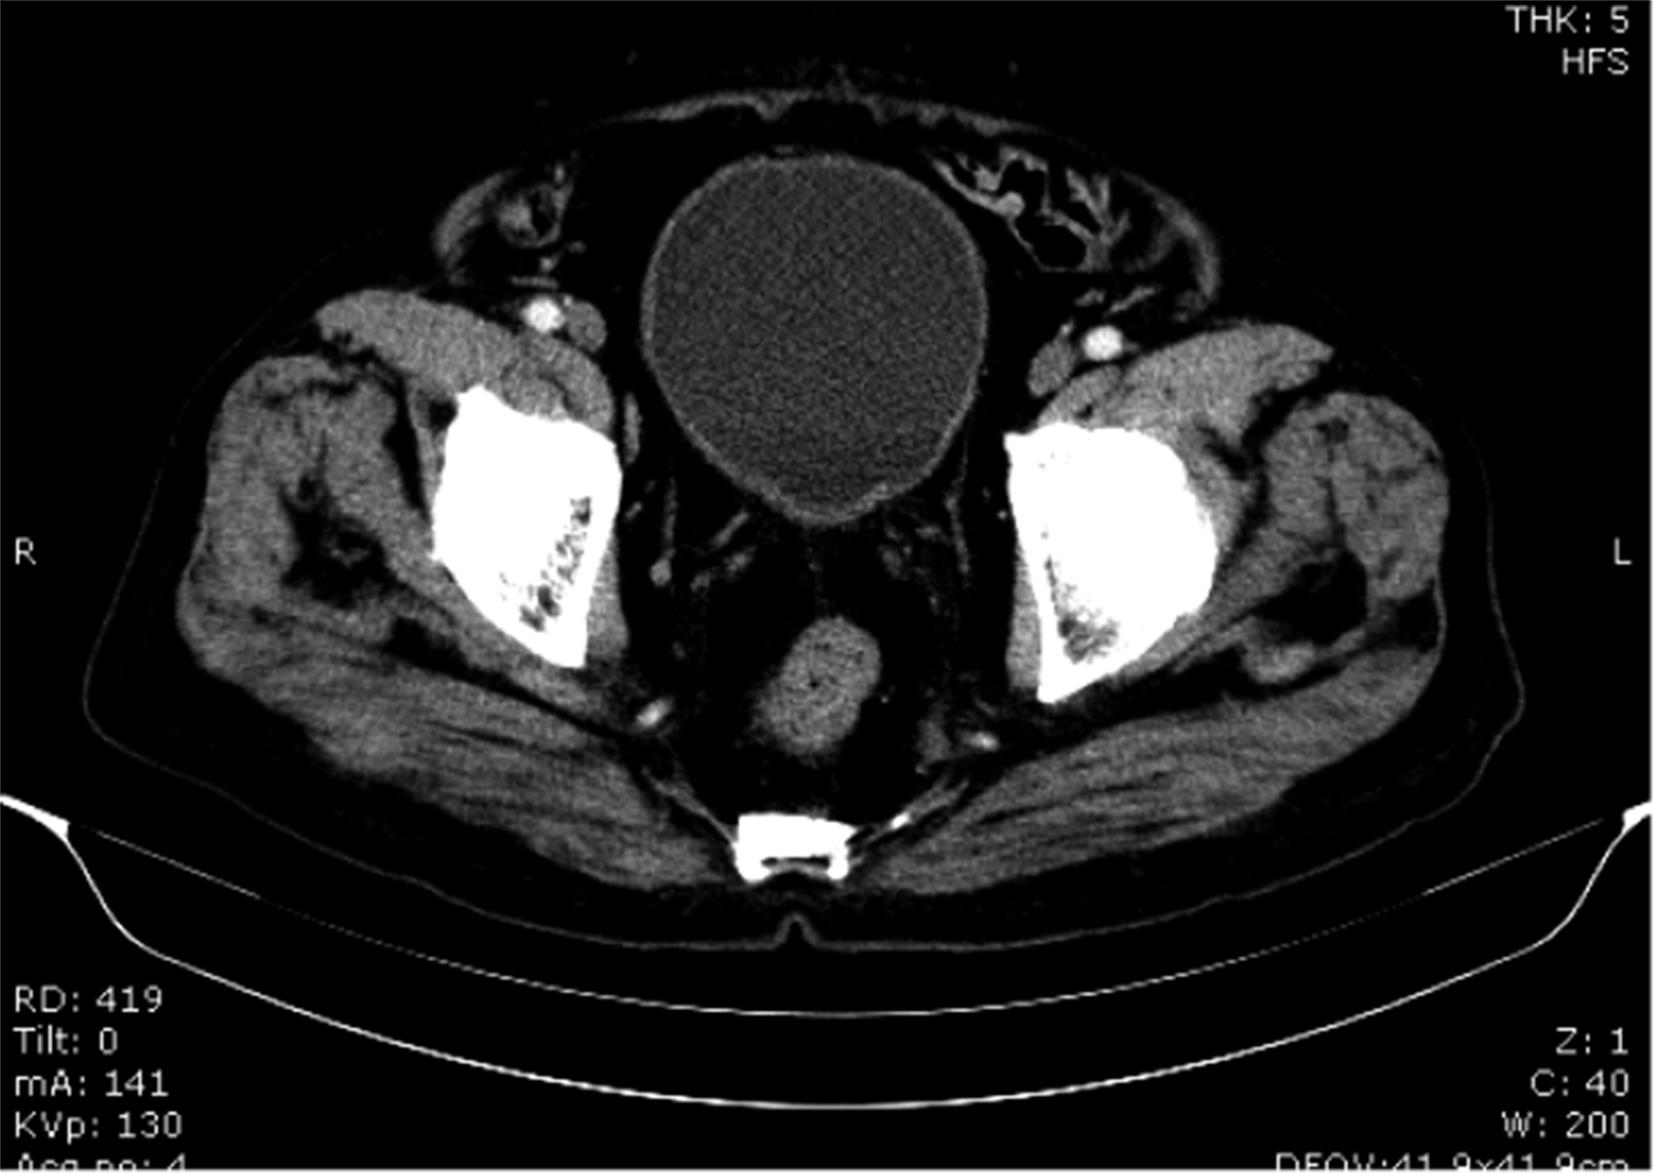

摘要:目的 探寻无法接受根治性手术治疗及放化疗的肌层浸润性膀胱癌病例的有效辅助治疗方式。方法 回顾性分析近10年广安门医院泌尿科肌层浸润性膀胱癌出院病例,统计患者治疗方式及保留膀胱时间。结果 61.90%应用膀胱肿瘤介入栓塞联合经尿道膀胱肿瘤切除术及中药治疗的患者达到了保留膀胱时间大于3年的治疗效果。结论 应用中西医结合治疗方式可能辅助延长肌层浸润性膀胱癌患者保留膀胱时间,改善患者预后及生存质量。